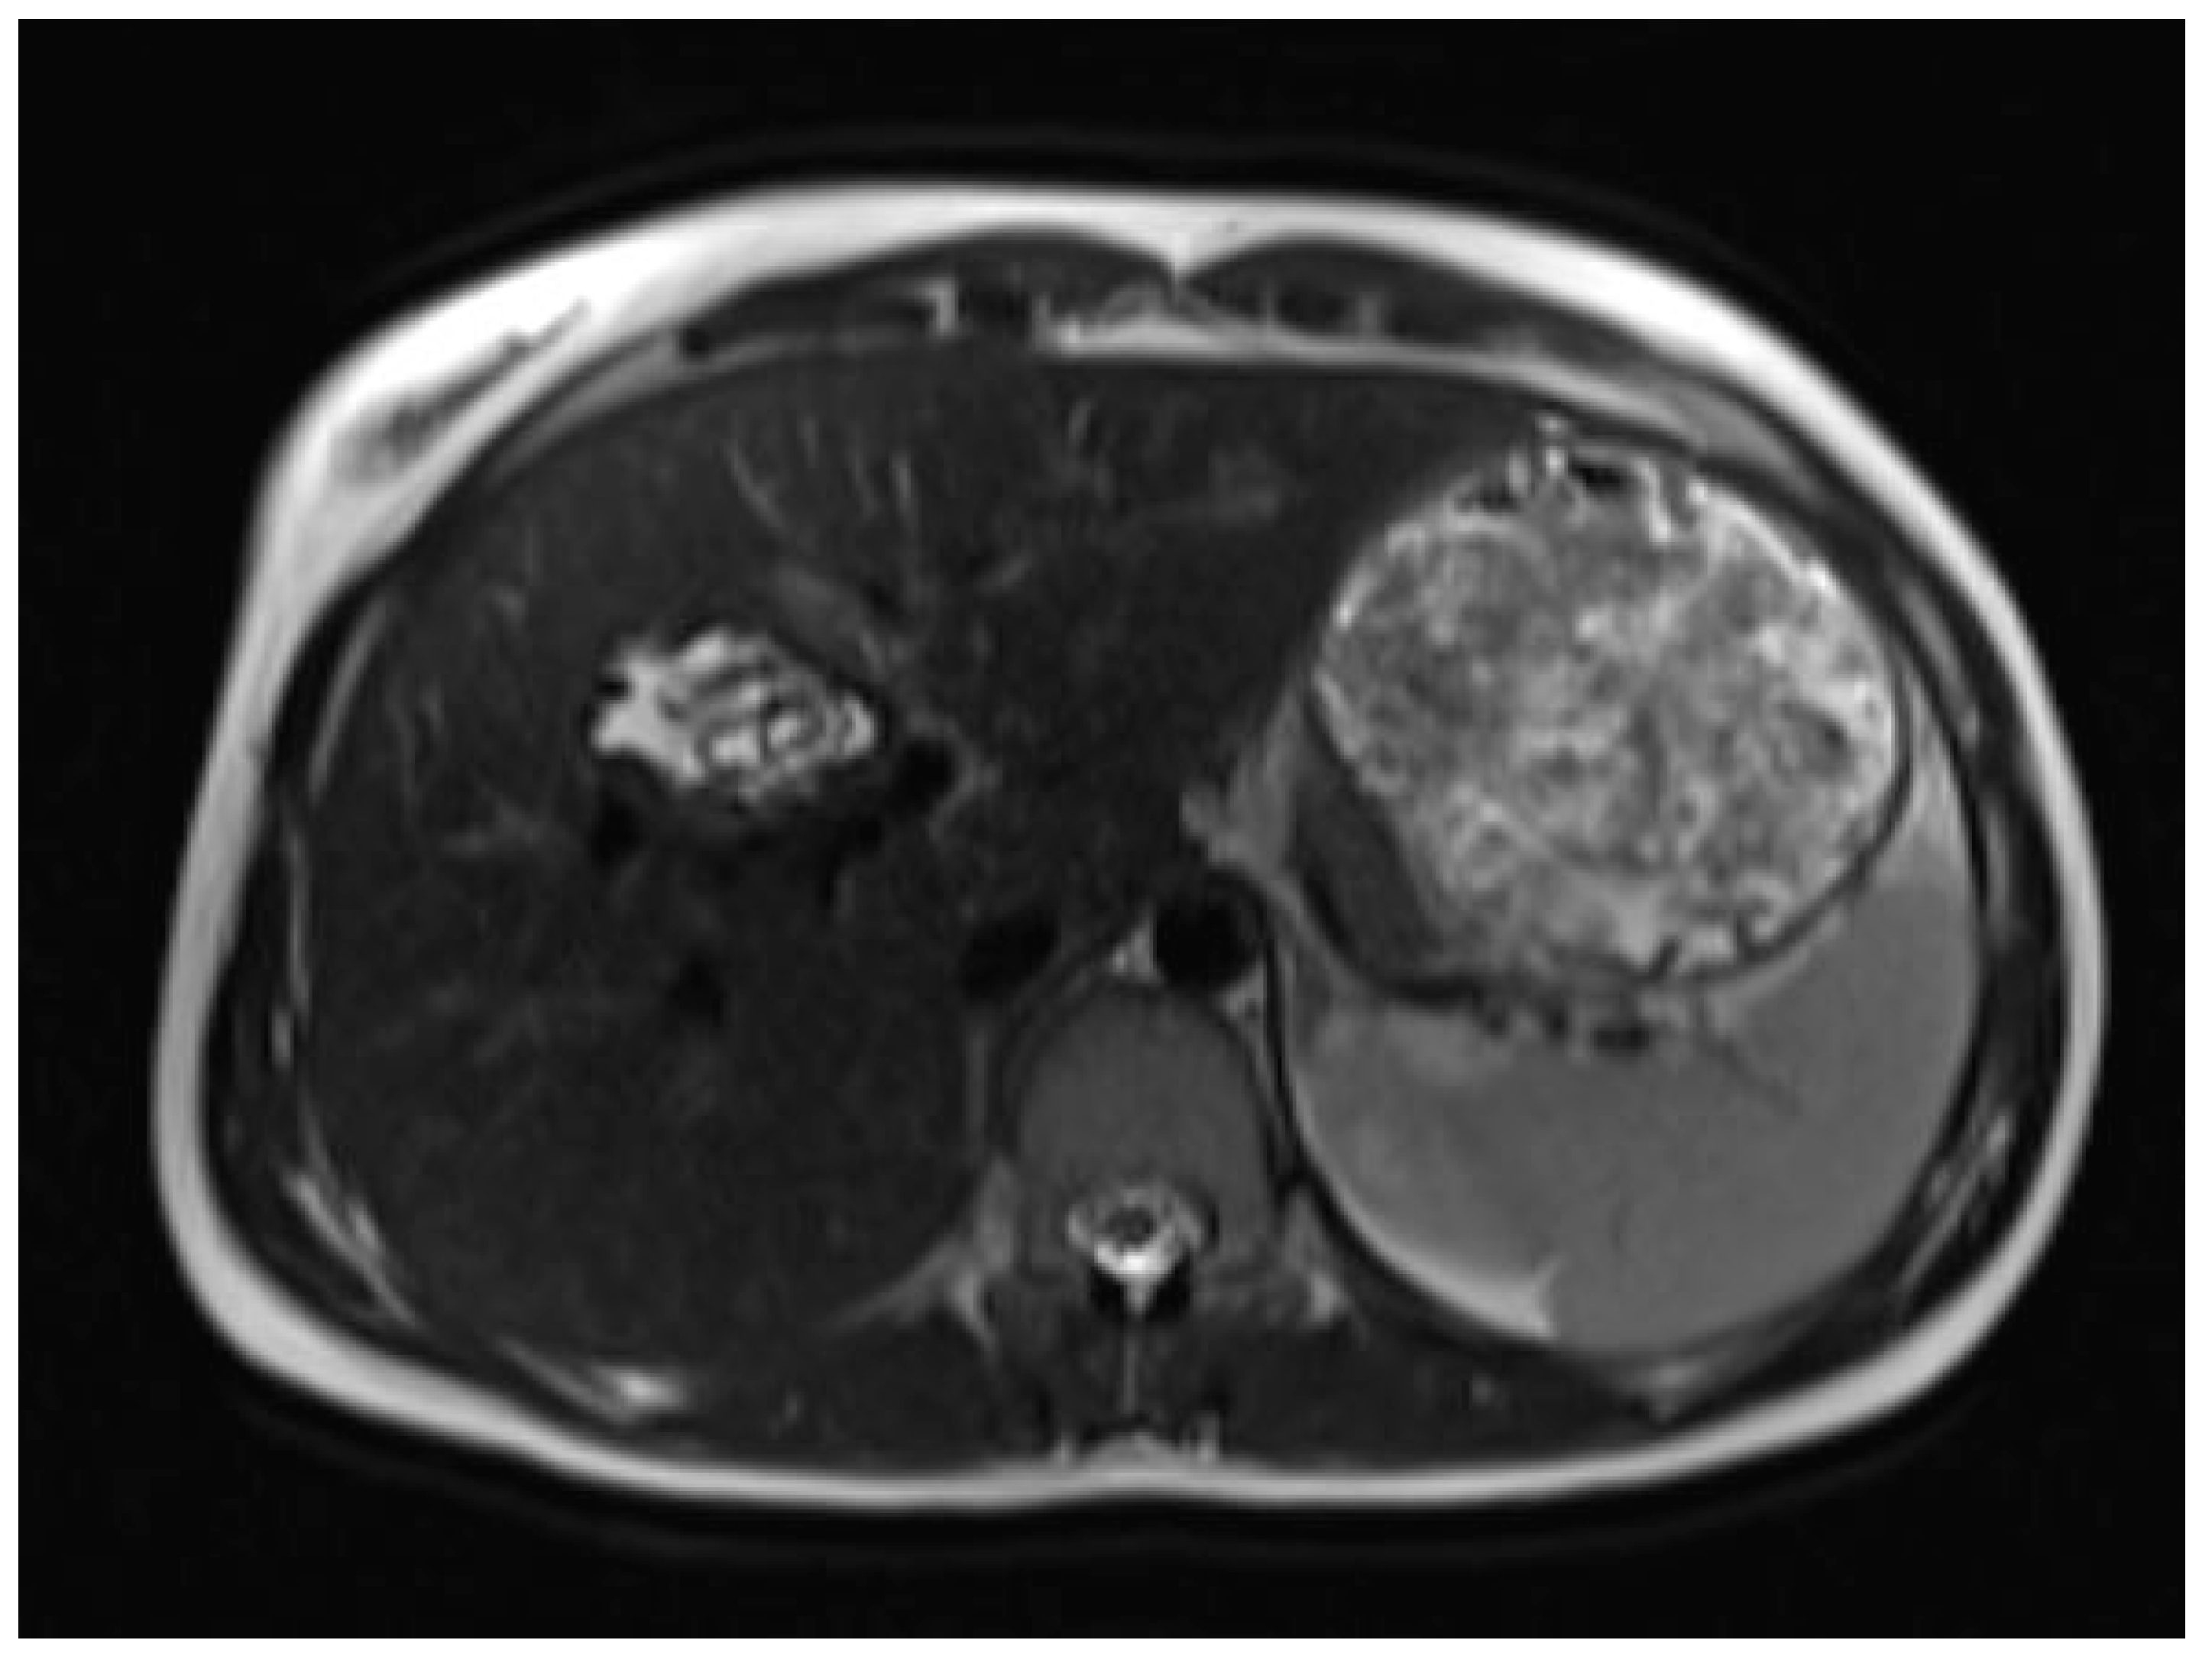

Six months later, a second ultrasound scan and a consecutive MRI scan to follow-up and control the success of the therapy were performed. The ultrasound revealed a decrease in the size of the cyst from 10 cm in maximal diameter to 9 cm and showed multiple circular septations, indicating an involuting cyst (Figure 7). In contrast to the preceding MRI scan, typical T2 hypointense membrane-like structures were observed within the lesion in T2WI. These represented most probably the floating membranes, the typical water-lily sign (Figure 8). T1WI (Figure 9) showed the cyst as a hypointense lesion, but the membranes could only be clearly observed in T2WI. Consecutively, the cyst was classified as WHO-CE3A.

Figure 8.

Second MRI scan: Axial T2W MRI scan, where floating membranes forming the water-lily sign after anthelmintic treatment, indicating stage WHO-C3a.

Figure 9.

Second MRI scan: Axial T1W native MRI scan, where the floating membranes are rather difficult to depict, with the hypointense area in liver segment IV showing the cyst.

MR imaging clearly visualizes pericyst, matrix, and daughter cysts. The pericyst appears as a hypointense rim on both T1WI and T2WI due to its fibrous structure and the presence of calcifications. This is a specific feature of hydatid cysts, called the rim sign, mostly better visualized on T2WI [5]. The matrix represents hydatid-fluid-containing membranes of broken daughter vesicles, scolices, and hydatid sand [7]. The hydatid matrix appears hypointense on T1WI and significantly hyperintense on T2WI. However, the limitations of MRI scans are especially observed in stages CE4–CE5, as bigger calcifications are better observed on a CT scan. When daughter cysts are present, they are typically more hypointense than the matrix on T2WI, as observed in our case report [17] (Figure 1). If the membrane is separated, it can shift with movement, resembling a water lily floating on the surface of a pond, previously described as water-lily sign, which was seen in our case report as well [18] (Figure 8).